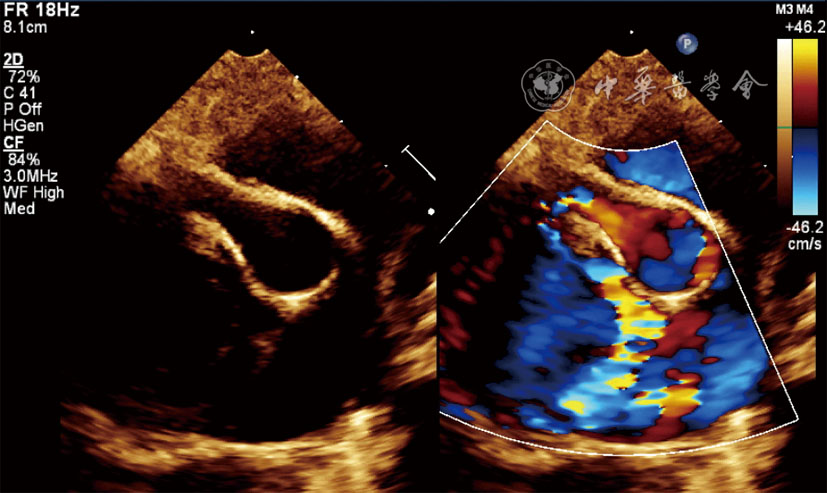

图1 胸骨旁大动脉短轴切面超声图像示右冠状动脉呈巨大瘤样扩张,瘘管走行迂曲